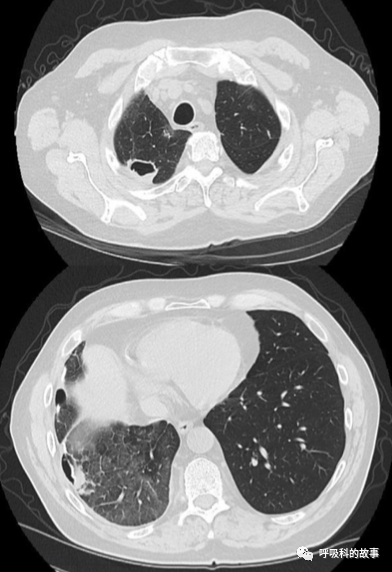

隨後的胸部CT掃描顯示右肺瀰漫性磨玻璃陰影(GGO),左下葉背段有一個1.5釐米的實性結節,邊緣有毛刺(圖2)。最初的支氣管鏡檢查結果為陰性,CT掃描結果為瀰漫性GGOs,這讓主管醫生考慮是隱源性機化性肺炎(COP),開始用每天60毫克的潑尼松治療患者,之後逐漸減量。

可是,患者的情況卻沒有絲毫改善,3個月後複查胸部CT,發現右肺出現新的大的空洞性病變,GGO惡化,縱膈淋巴結腫大,但左肺結節穩定(圖3)。